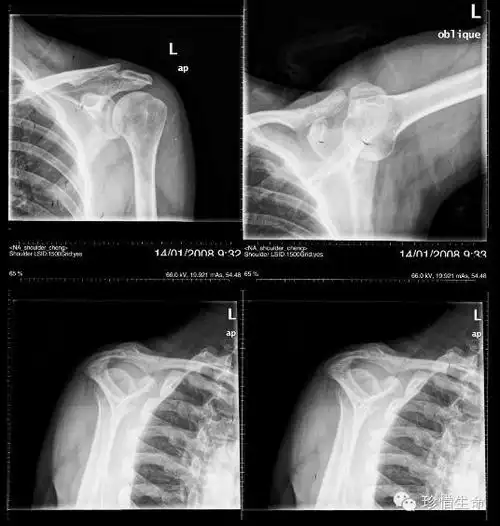

肩关节x线检查体位大全

骨肌左肩关节病变请会诊

中年女性,发现右肩关节占位2天.有特征,有细节---(有结果)